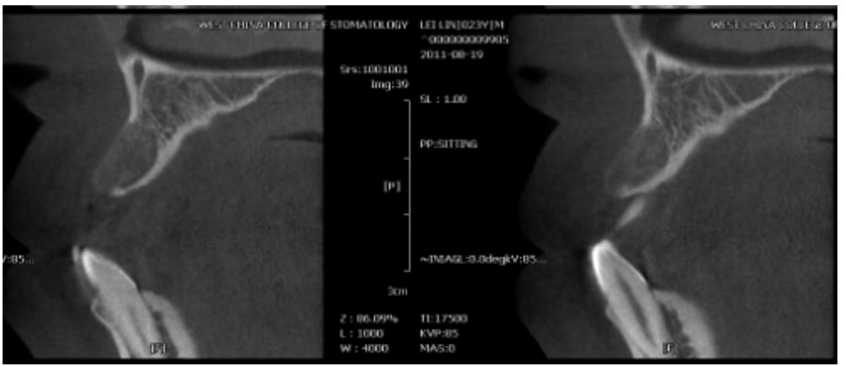

同一个患者前牙区的牙槽骨在不同的位置层面其牙槽骨形状也不一致;

图10 术前CBCT片矢状位显示在不同的层面上颌前牙区的牙槽骨形状不一致

图11 术前CBCT片矢状位显示在不同的层面上颌前牙区的牙槽骨形状不一致,牙槽窝未完全恢复